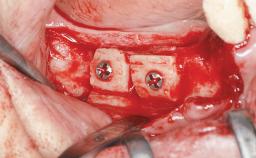

Shell Technique for Horizontal and Vertical Maxillary Bone Augmentation in a Partially Edentulous Patient with Aggressive Periodontal Disease

Bone Augmentation Horizontal|Staged|Vertical

Augmentation Materials Autogenous chips|Autogenous block(s)|Xenogenous